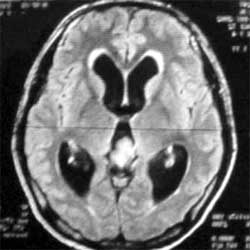

遺傳性黏多糖貯積症2.CT與磁共振(MRI)可準確地了解包括大腦、脊柱、骨(軟骨)、關節、呼吸道及心血管系統等結構改變的程度和範圍。二者均可清楚地顯示顱骨發育不良、大腦白質改變、腦積水、蛛網膜下腔狹窄、蛛網膜囊腫、顱頸關節的硬腦膜增厚、脊髓壓縮等。但在腦白質檢查方面,磁共振較CT更為敏感和可靠。通常,病程越長則CT與磁共振檢查的改變越明顯。